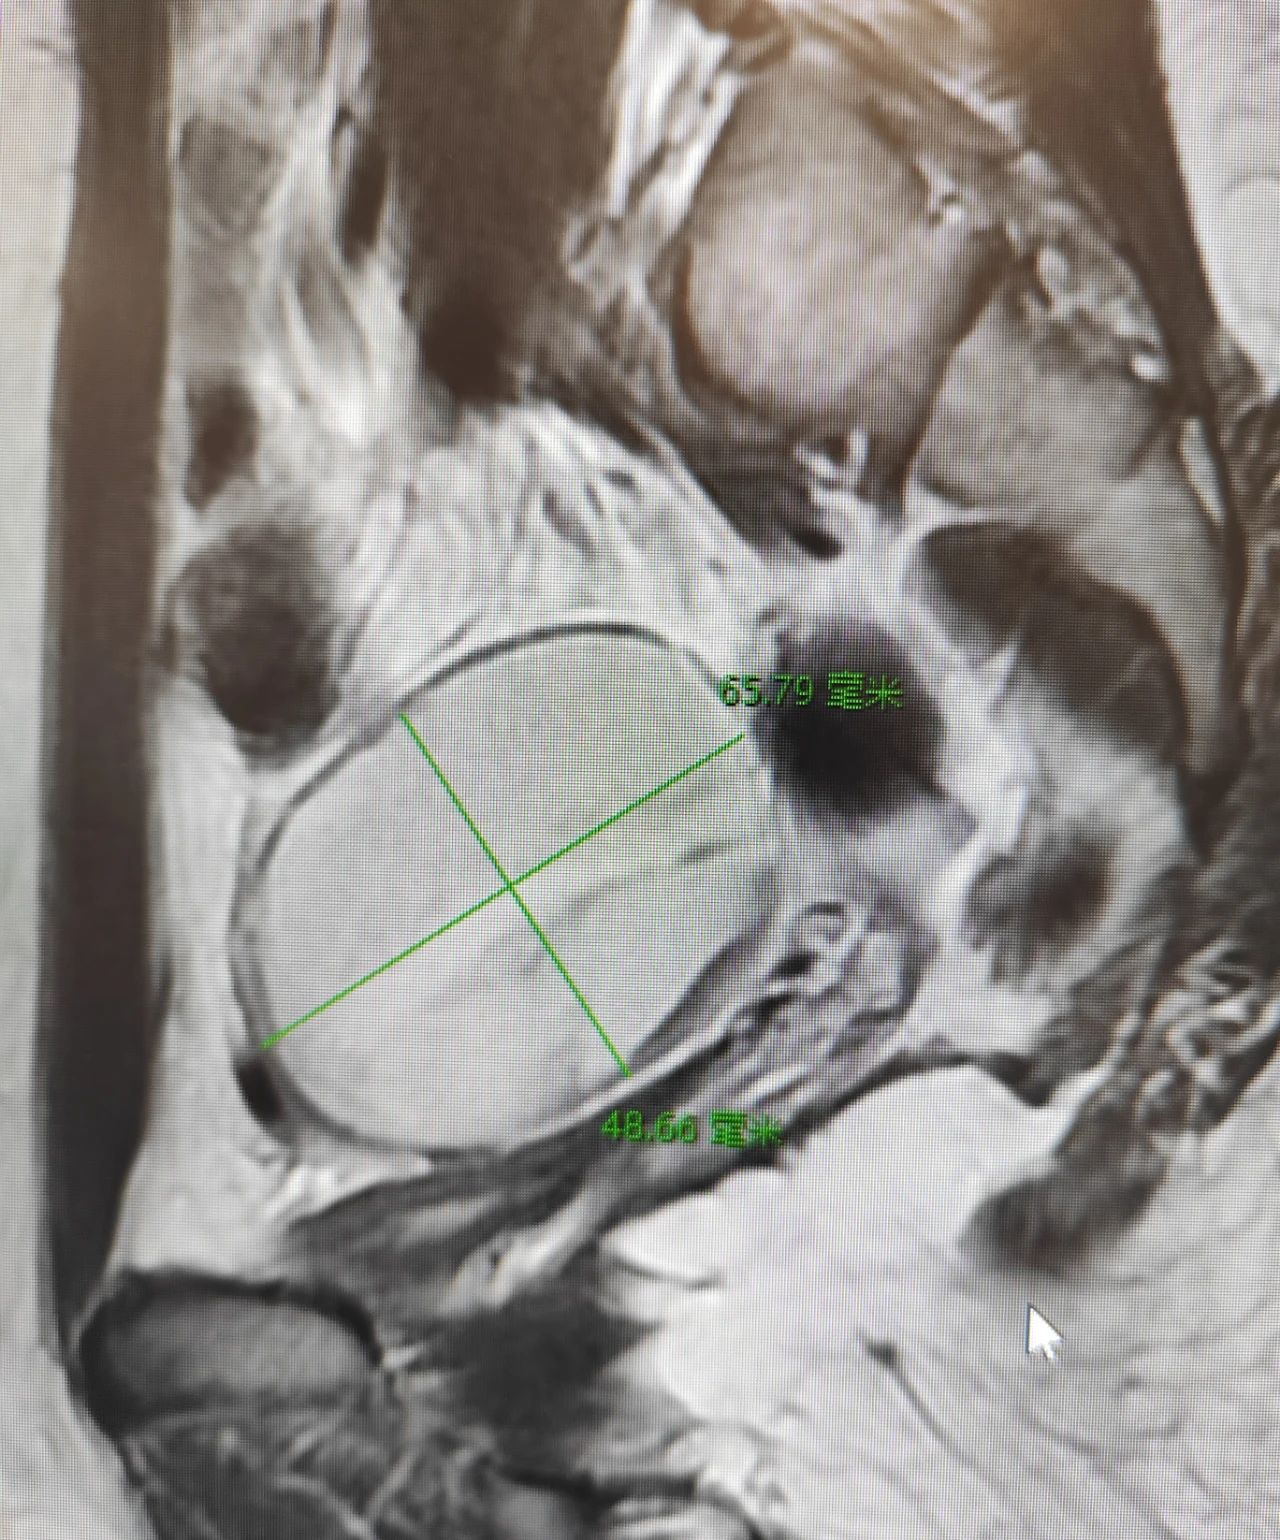

影像磁共振图片显示